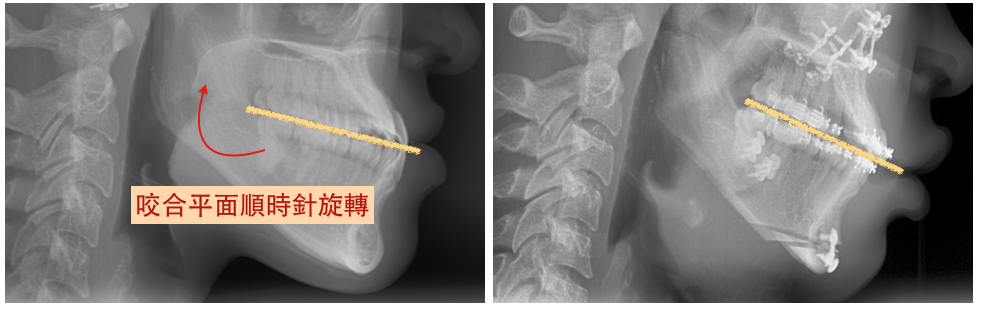

利用正顎手術將突出的上顎或下顎後縮,再配合咬合平面順時鐘旋轉做出微笑曲線,可以很自然得使嘴唇放鬆,改善唇形的問題。